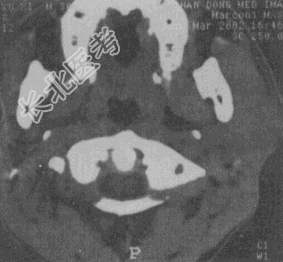

- 单项选择题女性,45岁。发现左侧腮部肿块1年余, 逐渐长大,无明显不适。CT检查如图所示, 应首先考虑

A、腮腺囊腺淋巴瘤

B、血管瘤

C、脂肪瘤

D、淋巴瘤

E、多形性腺瘤